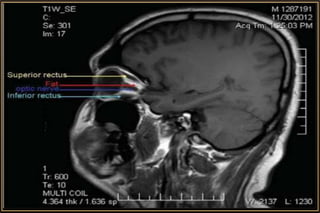

• Better for soft tissue

• Not ideal to visualise Bony manifestations

• Better resolution of Optic Nerve & Orbital Apex

• No radiation

• Must screen for metallic foreign bodies in orbit

Magnetic Resonance Imaging